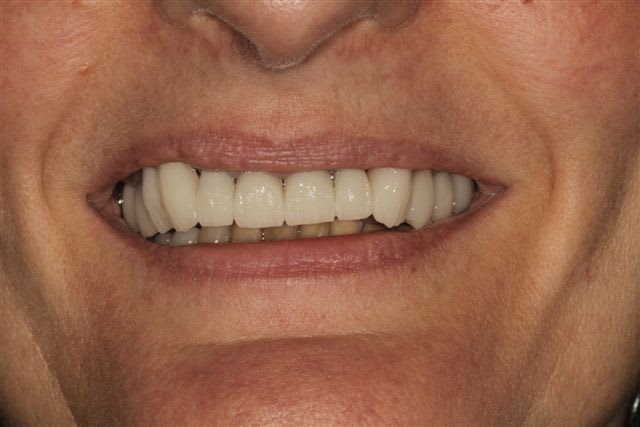

La suite, les soins ont commencés le 07/08.

Postérieur bas (16/08)et haut (14/09) en place, essayage des Emax avec "cutback".

Pour la teinte la patiente exige B1, sans maquillage, elle n'a pas attendu 47 ans pour que ça ne soit pas Blanc de blanc, alors là dessus j'ai cédé.

Cas typique de patient refusant l'ortho avant la réhabilitation global, avec un résultat esthétique ....disons que j'aime pas, bon si la patiente est contente!

Moi en tout cas au prochain patient qui refuse l'ortho nécessaire avant la réhabilitation globale, je lui montre ce cas. Merci encore je pense que cela sera utile.

Peut-on encore à ce stade diminuer (fortement) le volume des canines, réaligner les faces vestibulaires des PM droites, augmenter le volumes des centrales et distaliser les latérales???

Une petite élongation coronaire sur 11 et 21 n'aurait pas été de refus si racine pas trop courte.

1) la patiente a une paralysie faciale (levre superieure gauche). Le fait que les canine-premolaires-molaires cote II soient plus longues que les incisives accentue ce probleme.

Je raccourcirais ttes les dents de 23 à 26 de 2mm.

2) Axe de 13 pas bon. trop de bombe vestibulaire. Peut etre que la dent n'est pas assez taillee. En tout cas je la trouve trop dominante dans le sourire.

Les 2 canines sont effectivement très massives... Après tu fais avec les moyens que la patiente te donne, évidemment, mais là pour le coup je trouve pas ça très beau non plus.